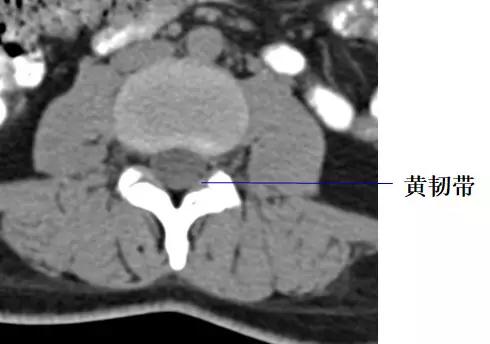

黄韧带较厚(正常时≤3mm),位于椎板和关节突的内侧面,密度高于硬脊膜囊和硬膜外脂肪,显示较清晰。

黄韧带厚约2~4mm,超过5mm为肥厚。